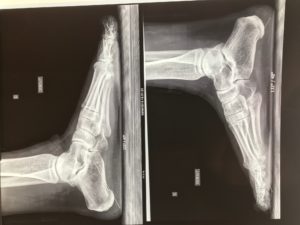

The pre-therapeutic check-up includes standard x-rays in charge (adult osteoarthritis research), and most often an ultrasound or an MRI to specify in particular the condition of the posterior tibial tendon.